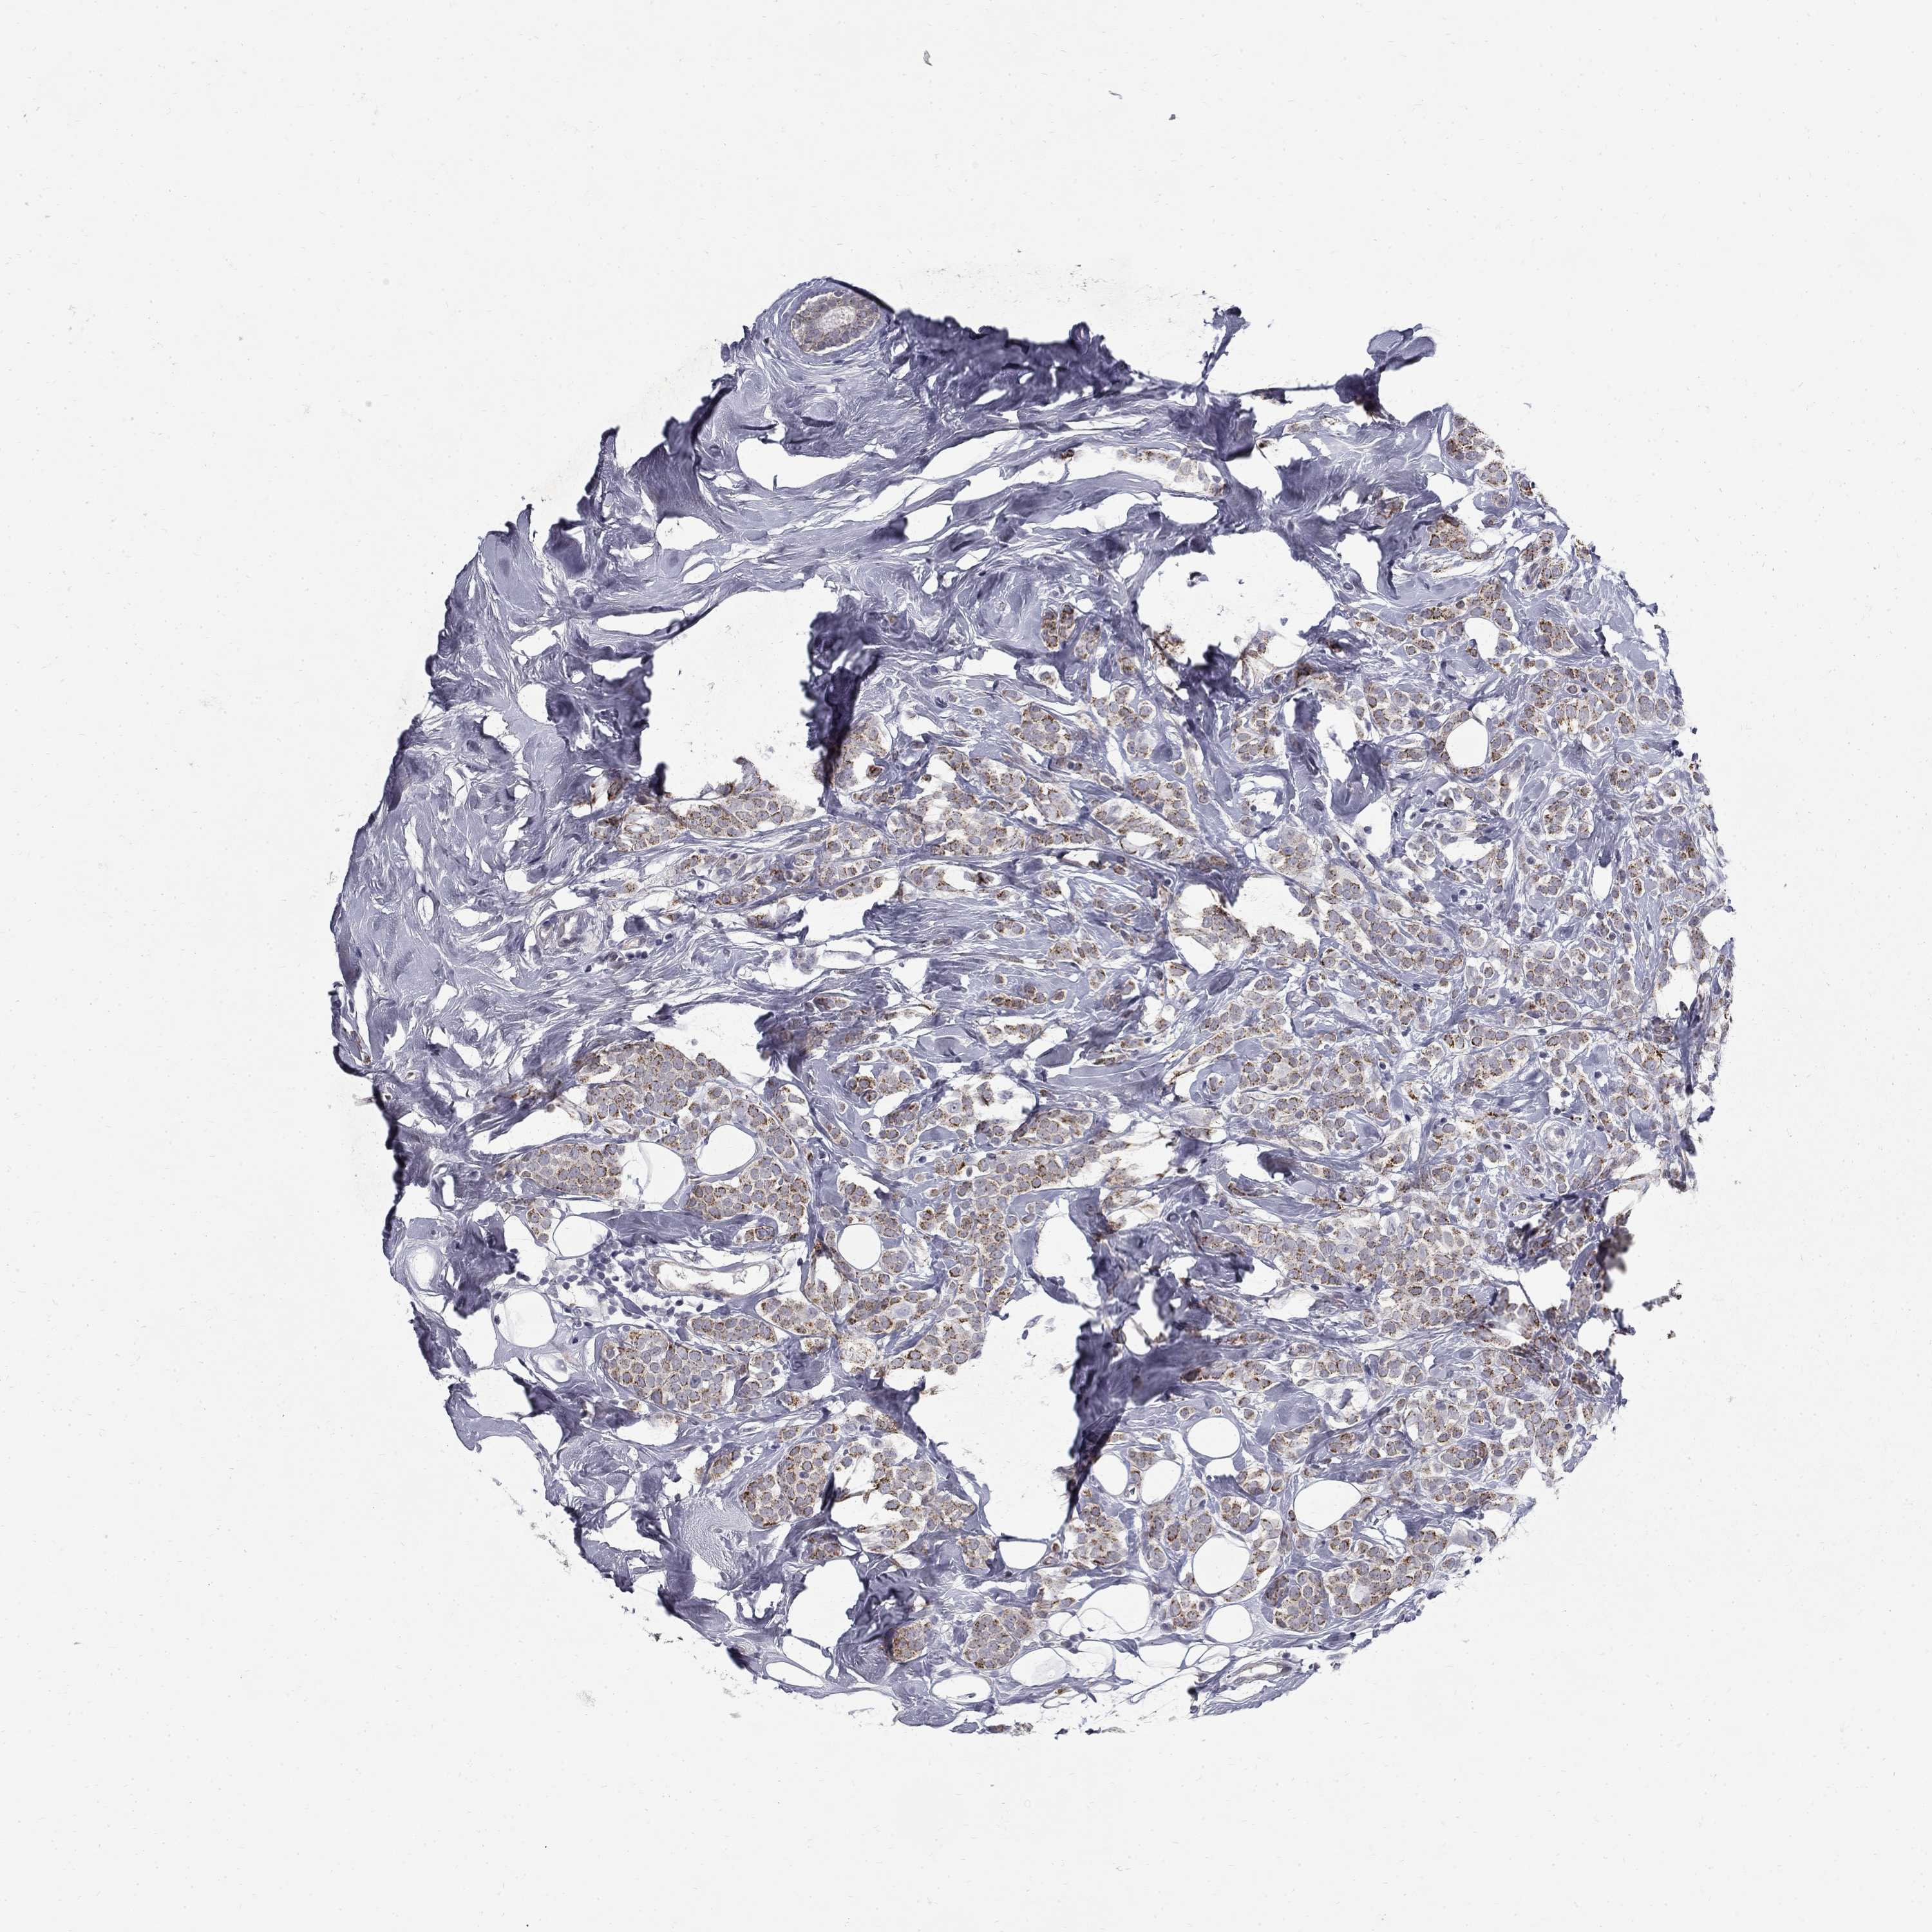

BRCA TCGA BRCA VALIDATION PROTEIN EXPRESSION